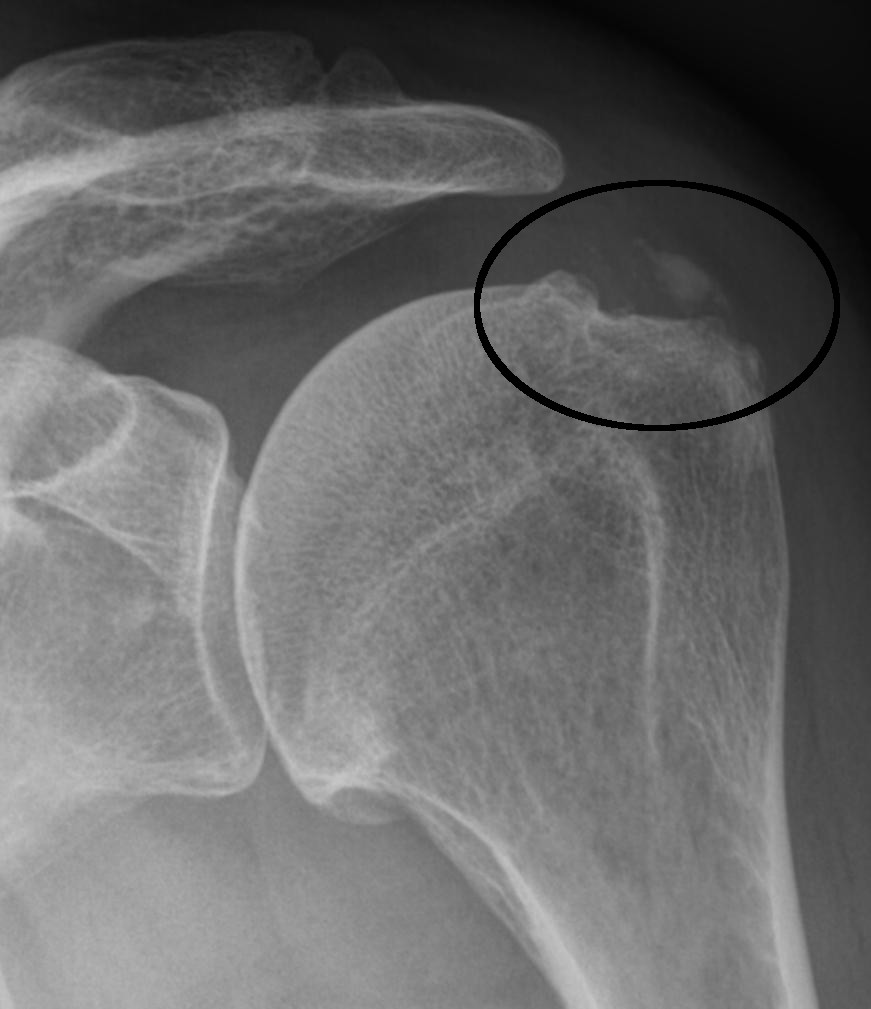

L'épaule calcaire, également appelée tendinose calcifiante, est une affection douloureuse de l'épaule. Elle est due à des dépôts de calcaire dans les tendons de la coiffe des rotateurs, un groupe de muscles responsable de la mobilité de l'épaule.

Diagnostic : Comment diagnostiquer l'épaule calcifiée ?

Le diagnostic de l'épaule calcaire dans notre cabinet orthopédique privé se caractérise par un soin particulier. Nous savons que le calcaire dans l'épaule ne provoque pas toujours des douleurs et inversement. C'est pourquoi notre première étape consiste en une anamnèse complète et un examen approfondi. Cette approche nous permet d'identifier les véritables causes de vos douleurs et de nous assurer que notre diagnostic est précis.

Des appareils à ultrasons ultramodernes nous permettent d'observer en détail les parties molles de votre épaule ainsi que les tendons de la coiffe des rotateurs. Dans certains cas, nous complétons ces examens par une IRM, qui ne peut certes pas représenter le calcaire, mais qui peut montrer une tendinite, des ruptures partielles ou une bursite de manière encore plus détaillée que l'échographie.